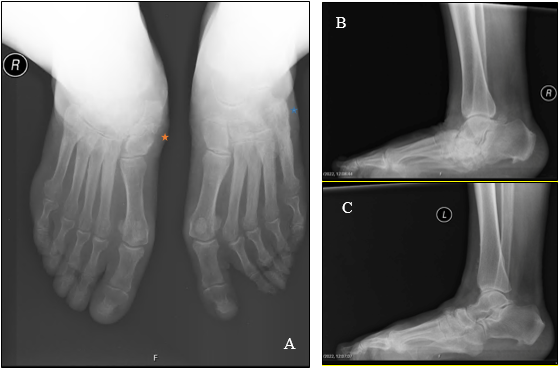

Charcot foot is often misdiagnosed due to lack of knowledge and poor understanding of the pathogenesis behind it.2,9,10 It is thought that Charcot foot develops due to recurring micro-trauma to the foot with sensitive deficit (neurotraumatic theory), and sympathetic denervation with peripheral vasodilation and formation of arteriovenous shunting causing the increase of osteoclastic activity (neurovascular theory).1,4,5,11 Their prevalence is increased with aging, obesity, neuropathy, foot trauma or surgery, increased haemoglobin A1c levels, renal failure, iron deficiency anaemia, osteoporosis, and rheumatoid arthritis.2,5 Charcot foot is classified clinical, anatomical and radiologically. Clinically, there is an active and inactive stage, with days to months of progression separating these two3. Active stage presents with increased temperature of >2 °C compared to the other foot, redness, oedema, palpable pulses and sometimes painful.3,7,12 Inactive stage is categorized as a progressively receding inflammation, finally leading to a rocker bottom deformity.3,6 For the anatomical classification, we use the classification proposed by Sanders and Frykberg (Figure 1) while for radiological classification we use the modified Eichenholtz classification (Figure 2).2,6

Figure 1 Anatomical classification of Sanders and Frykberg. Zone I: interphalangeal and metatarsophalangeal joints; II: tarsometatarsal joints; III: tarsal joints; IV ankle and subtalar joints; V: calcaneus. From Rosskopf et al.6